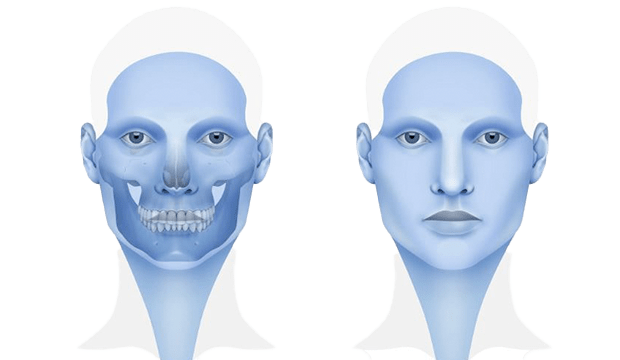

Çene cerrahı, çene kemiklerinde kesiler (osteotomi) yaparak çeneleri doğru pozisyona getirir. Çene hareketiniz tamamlandıktan sonra, kemikleri yeni (planlanan) konumlarına sabitlemek için kemik plakaları, vidalar, teller ve lastik bantlar kullanılır. Diş teli için kullanılan bir braketten daha küçük olan bu vidalar zamanla kemik yapısına entegre (kaynaşma) olurlar.

Bazı durumlarda çenelere fazladan kemik ekleme ihtiyacı olabilir. Bu durumda genellikle iliak adı verilen ön kalça kemiği bölgesinden kemik alınarak gerekli bölgeye plaklar ve vidalarla sabitlenir.

Çene ameliyatı üst çene, alt çene, çene ucu ( genioplasty) veya bunların herhangi bir kombinasyonu ile yapılır.